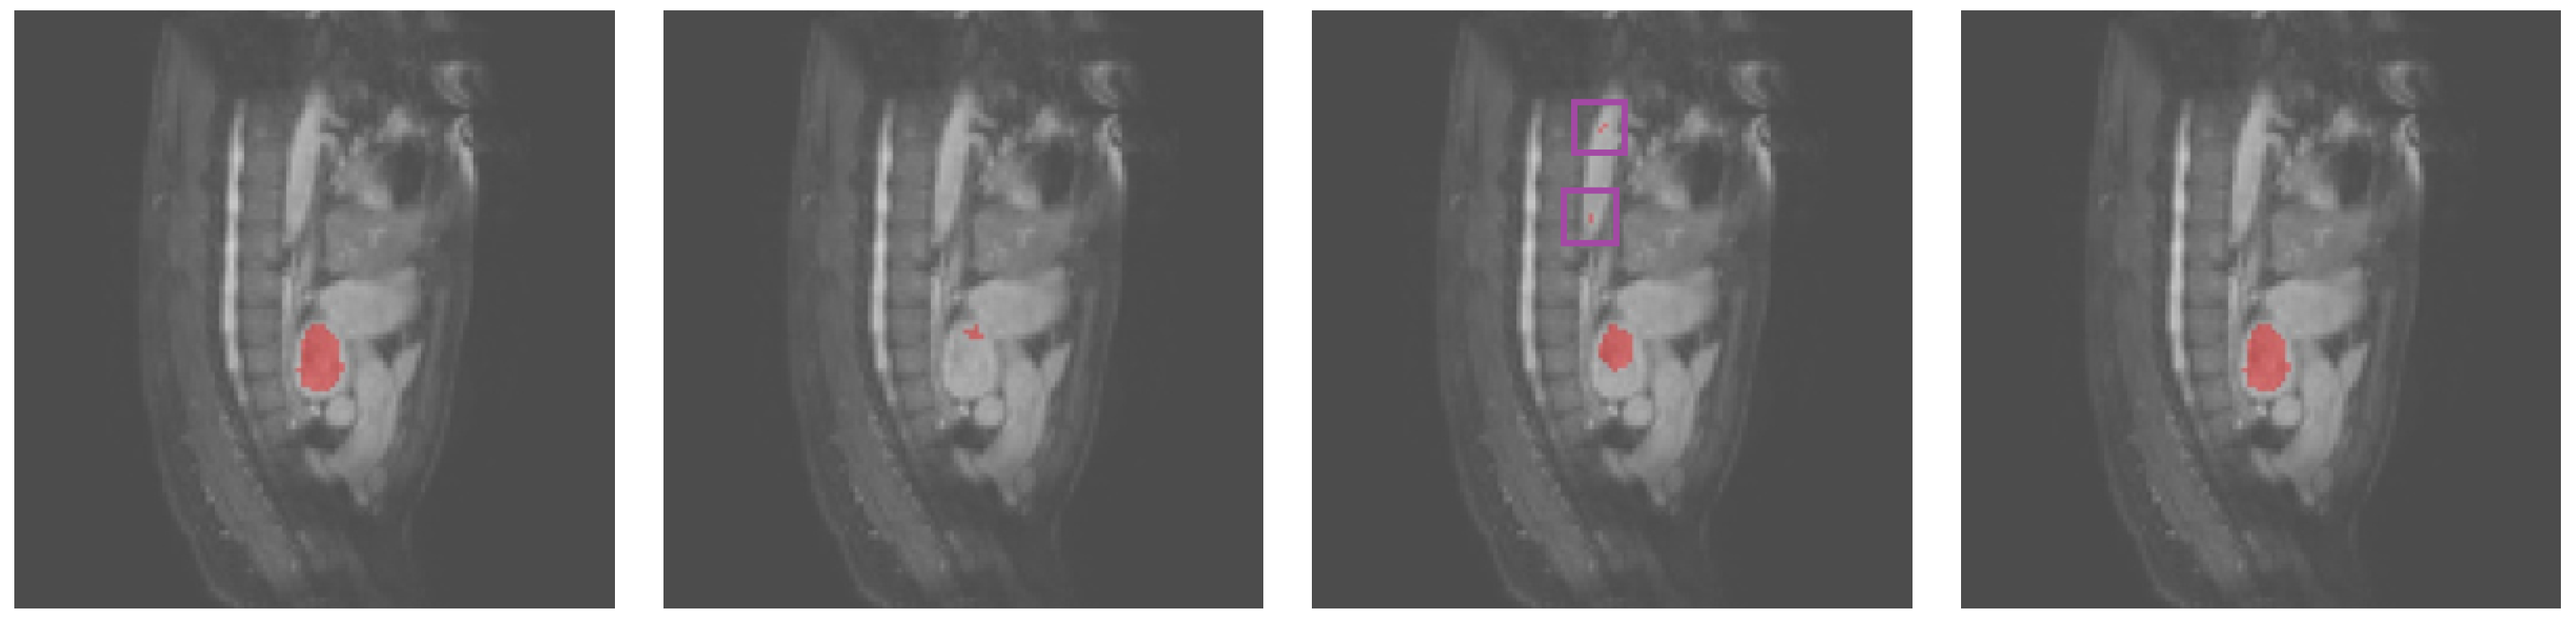

3.2. Results Obtained on the Heart MRI Dataset

| Dice | TPR | TNR | HD95 | |

|---|---|---|---|---|

| U-Net | 73.94% | 80.71% | 98.24% | 24.28 |

| UNet++ | 74.06% | 90.25% | 97.50% | 28.33 |

| Att-UNet | 72.82% | 83.74% | 97.84% | 27.39 |

| Focus-UNet | 68.03% | 87.79% | 96.72% | 39.92 |

| SAB-Net | 78.27% | 82.63% | 98.67% | 21.21 |